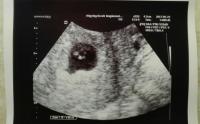

Jelentem az ultrahang megvolt,minden rendben van. 2,5mm-es, erős szívhang,a doki szerint minden olyan,amilyennek lennie kell :-) Annyira furcsa èrzès volt látni,a könnyem is kicsordult. Kèpet is kaptam,megpróbálom csatolni.